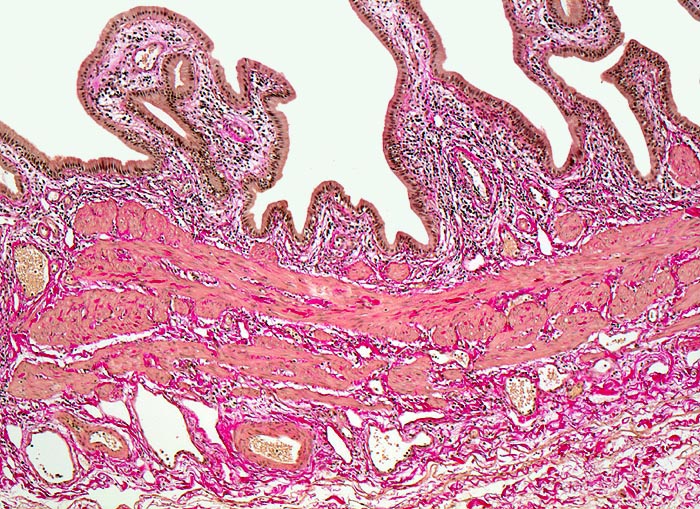

Normale Gallenblase

Die Gallenblasenschleimhaut bildet unregelmässige Falten, die bedeckt sind von einem hochzylindrischen Epithel. Auf die Mukosa folgt eine Schicht mit glatter Muskulatur. Am unteren Bildrand das Bindegewebe der subserösen Schicht.